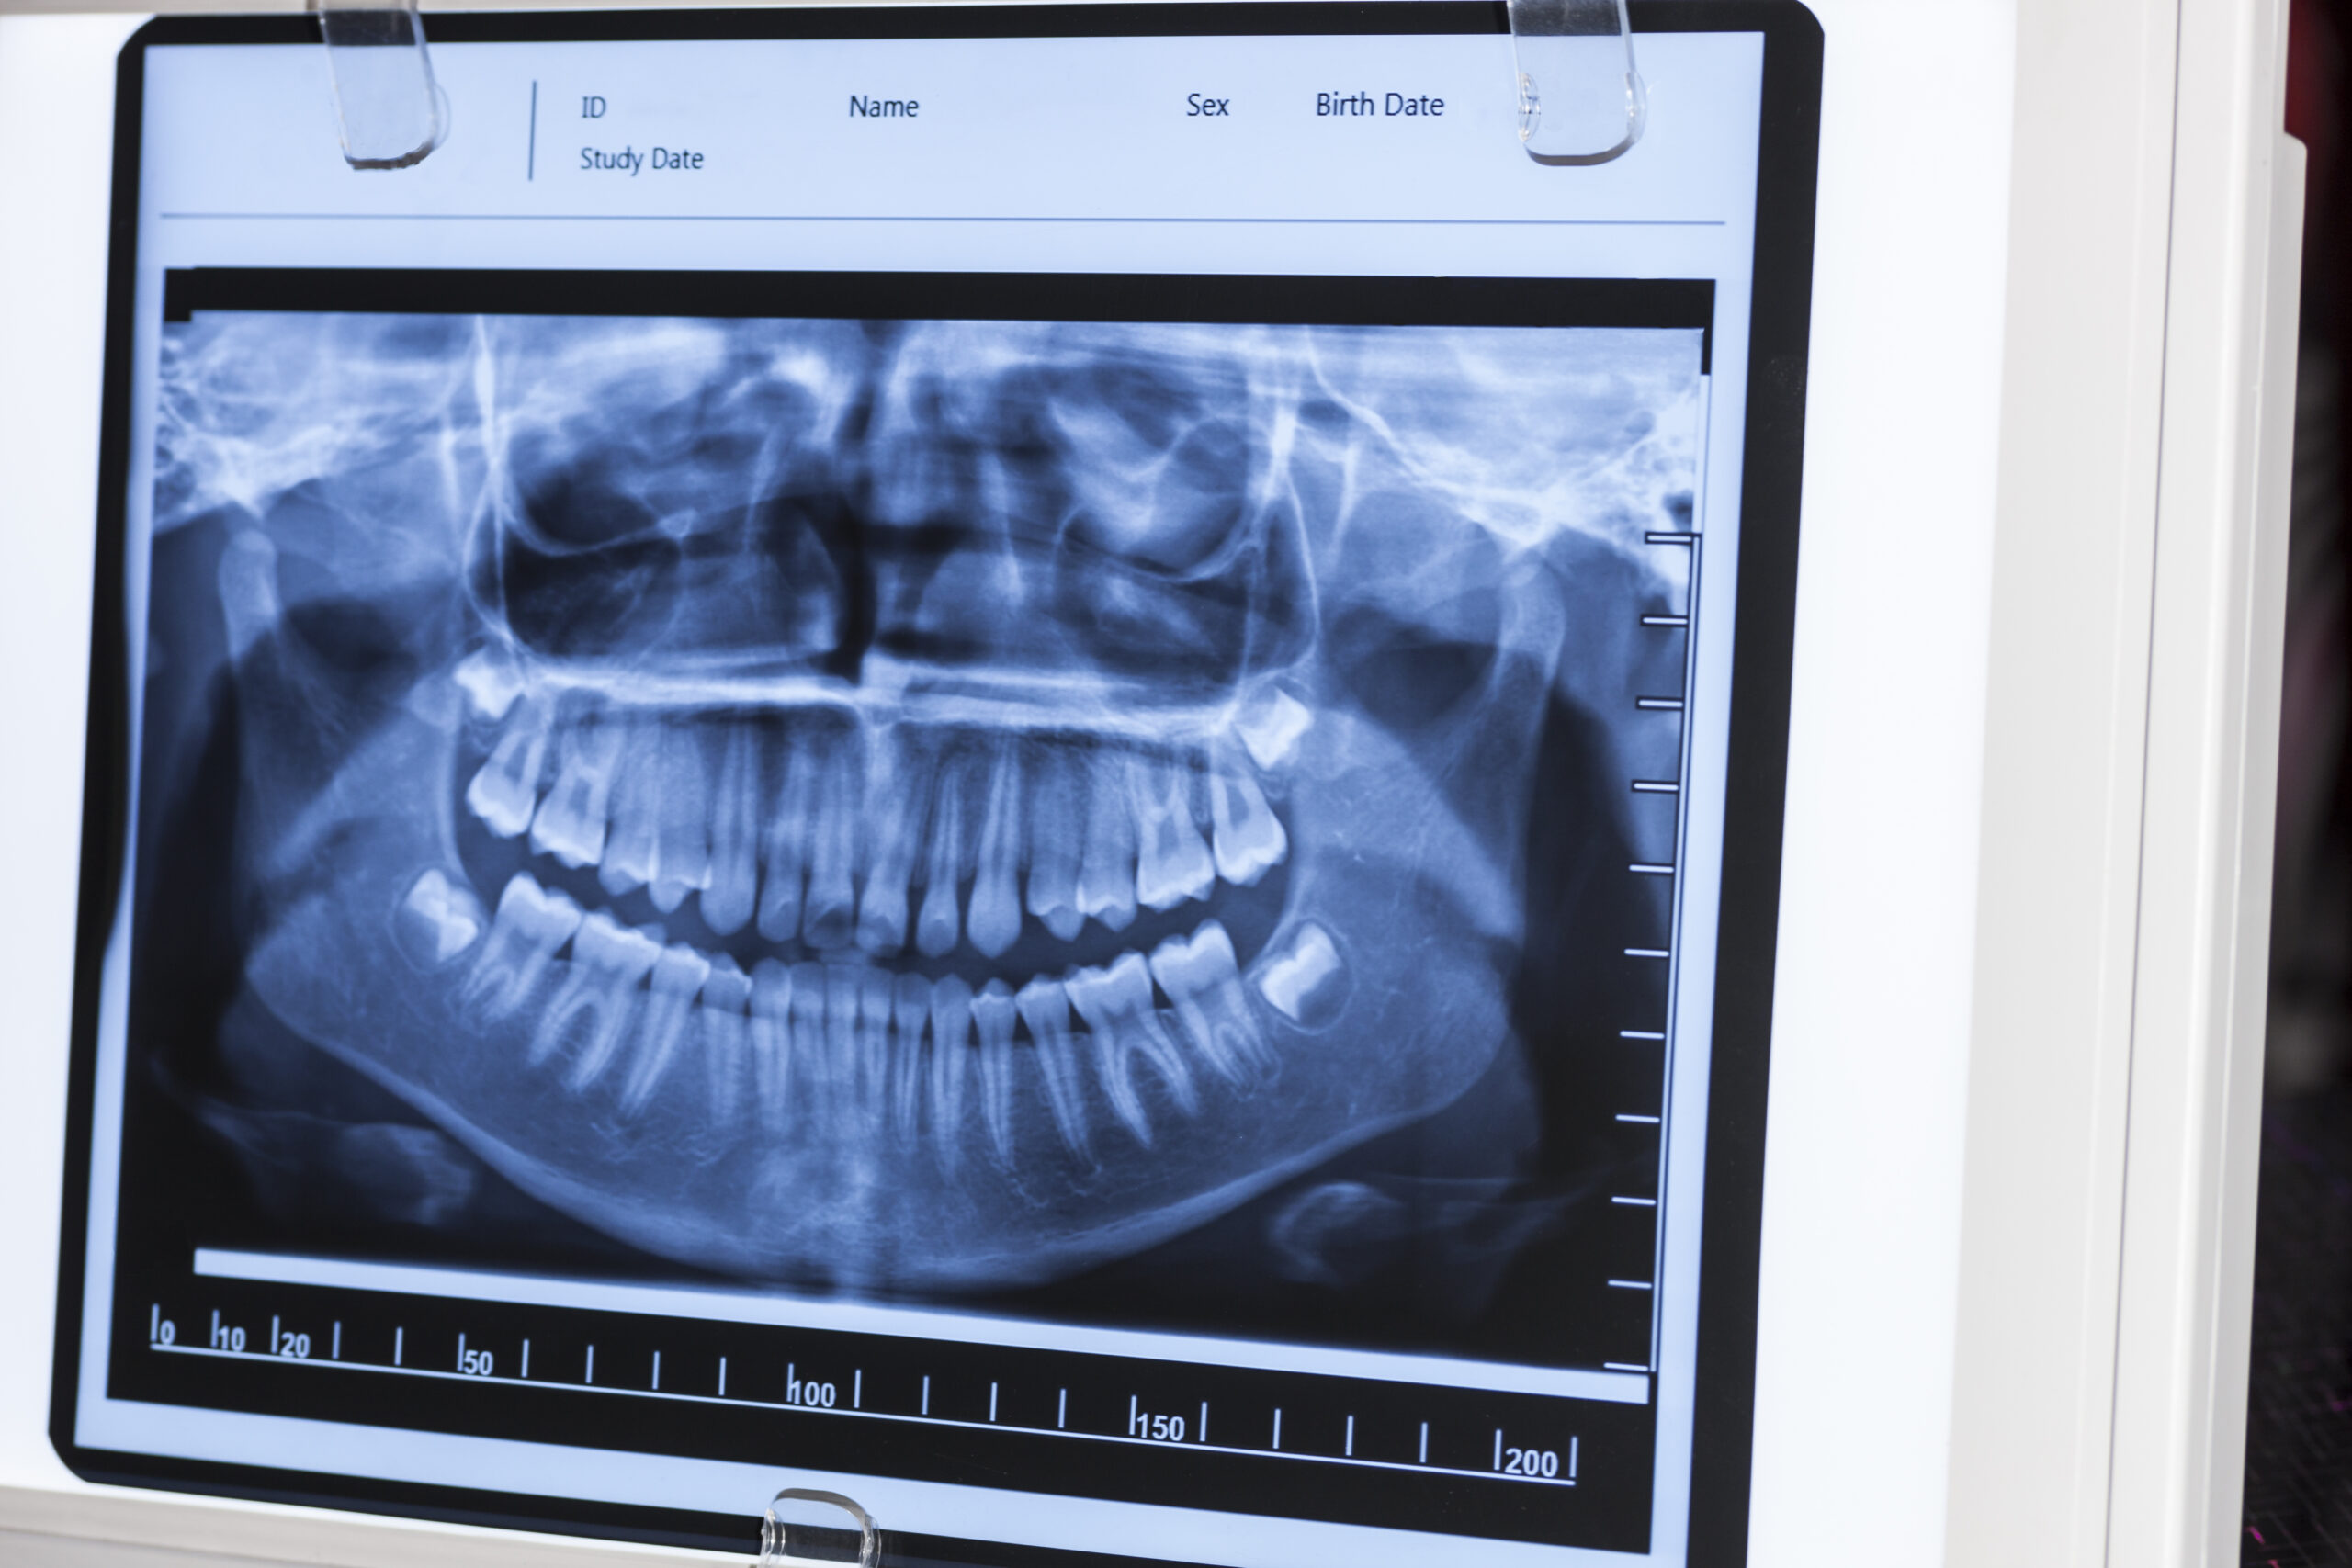

The panoramic X-ray procedure is an integral part of dental examinations and treatments. Unlike images that provide information about only a few teeth, panoramic X-rays capture the entire mouth in a single image, providing details not only about the upper and lower jaws but also the nasal cavity and sinus spaces. This comprehensive view gives the dentist all the necessary information and helps increase the success rate of treatments.

Dentists request a panoramic X-ray before planning treatment to detect any issues in the bone structure and to gain information about existing infections. With the support of advanced equipment, the procedure takes approximately 10 seconds, and based on the obtained data, the patient’s required treatment can be planned accurately, quickly, and thoroughly.

Panoramic X-rays provide a wide and detailed view of the area to be treated and are also requested before surgical interventions related to the jaws or teeth. Thanks to systems widely used worldwide for patients of all ages, cysts, tumors, cavities, and infectious problems in the relevant area can be detected in advance, ensuring that necessary treatments are successfully carried out.